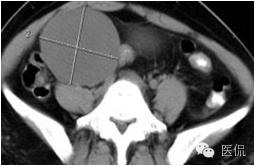

子宫阔韧带肌瘤